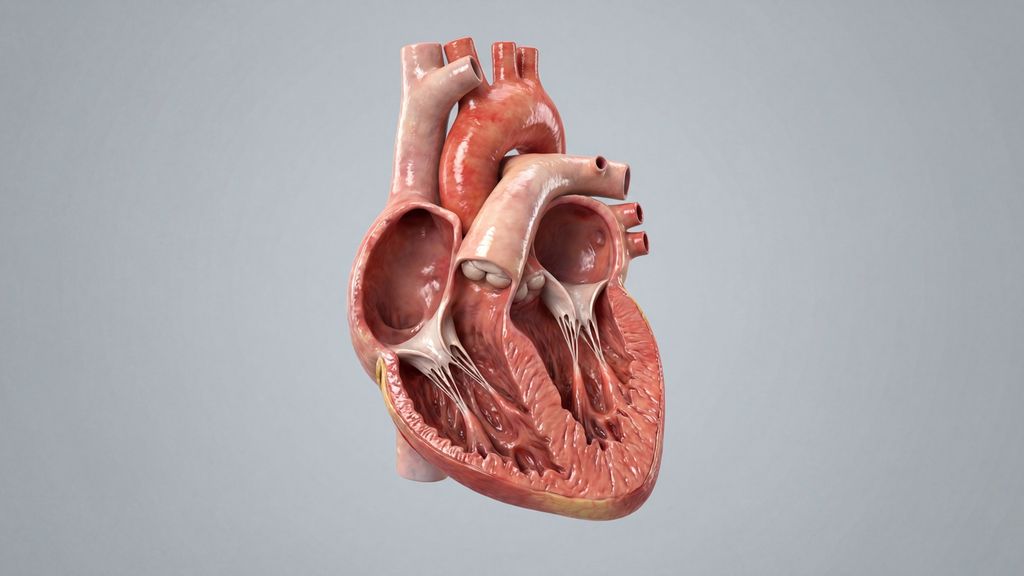

Bedeutung der Komorbiditätenin der Meniskuschirurgie

Bestimmte Risikofaktoren und Begleitkrankheiten können den Verlauf nach einer Meniskusverletzung massgeblich beeinflussen. Welche das sind, worauf man dabei achten sollte, warum das vor ...

Knorpeldefekte im Knie: AMIC zeigt kurzfristig bessere Ergebnisse als MCI

Knorpeldefekte im Knie können die Lebensqualität einschränken und langfristig zu Arthrose und der Notwendigkeit eines Gelenkersatzes führen. Es gibt diverse Behandlungstechniken, aber ...

Diagnostik und Therapie der Kniegelenkluxation

Luxationen des Kniegelenks sind sehr seltene, aber schwerwiegende Verletzungen, die häufig mit Komplikationen einhergehen und unbehandelt zu schweren Instabilitäten im Knie führen können ...